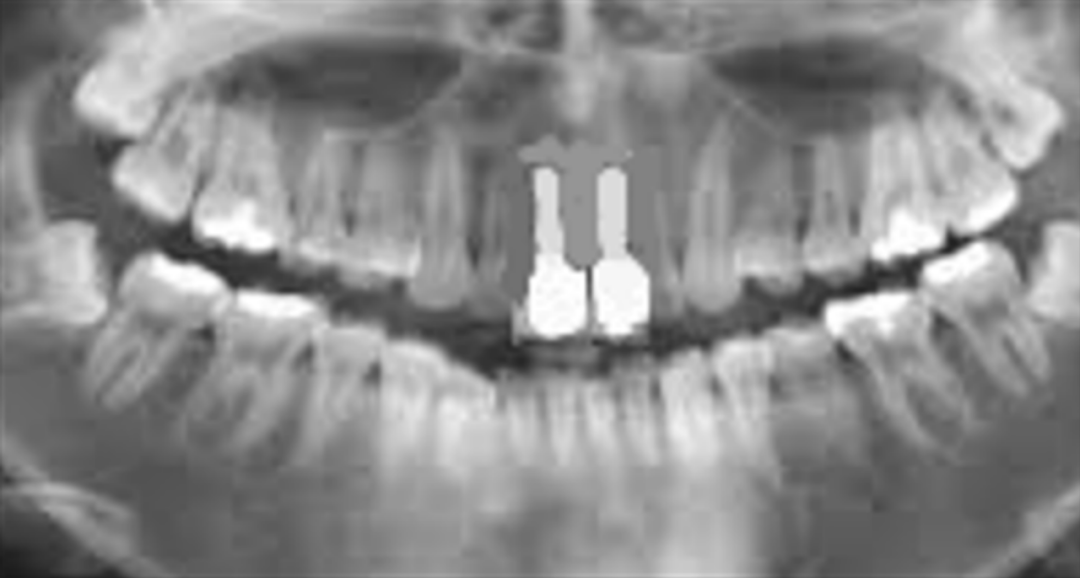

(图 / 患者植入植体 本图版权为祯诺ZENOIS,由好牙医提供)

(图 / 患者种牙效果 本图版权为祯诺ZENOIS,由好牙医提供)